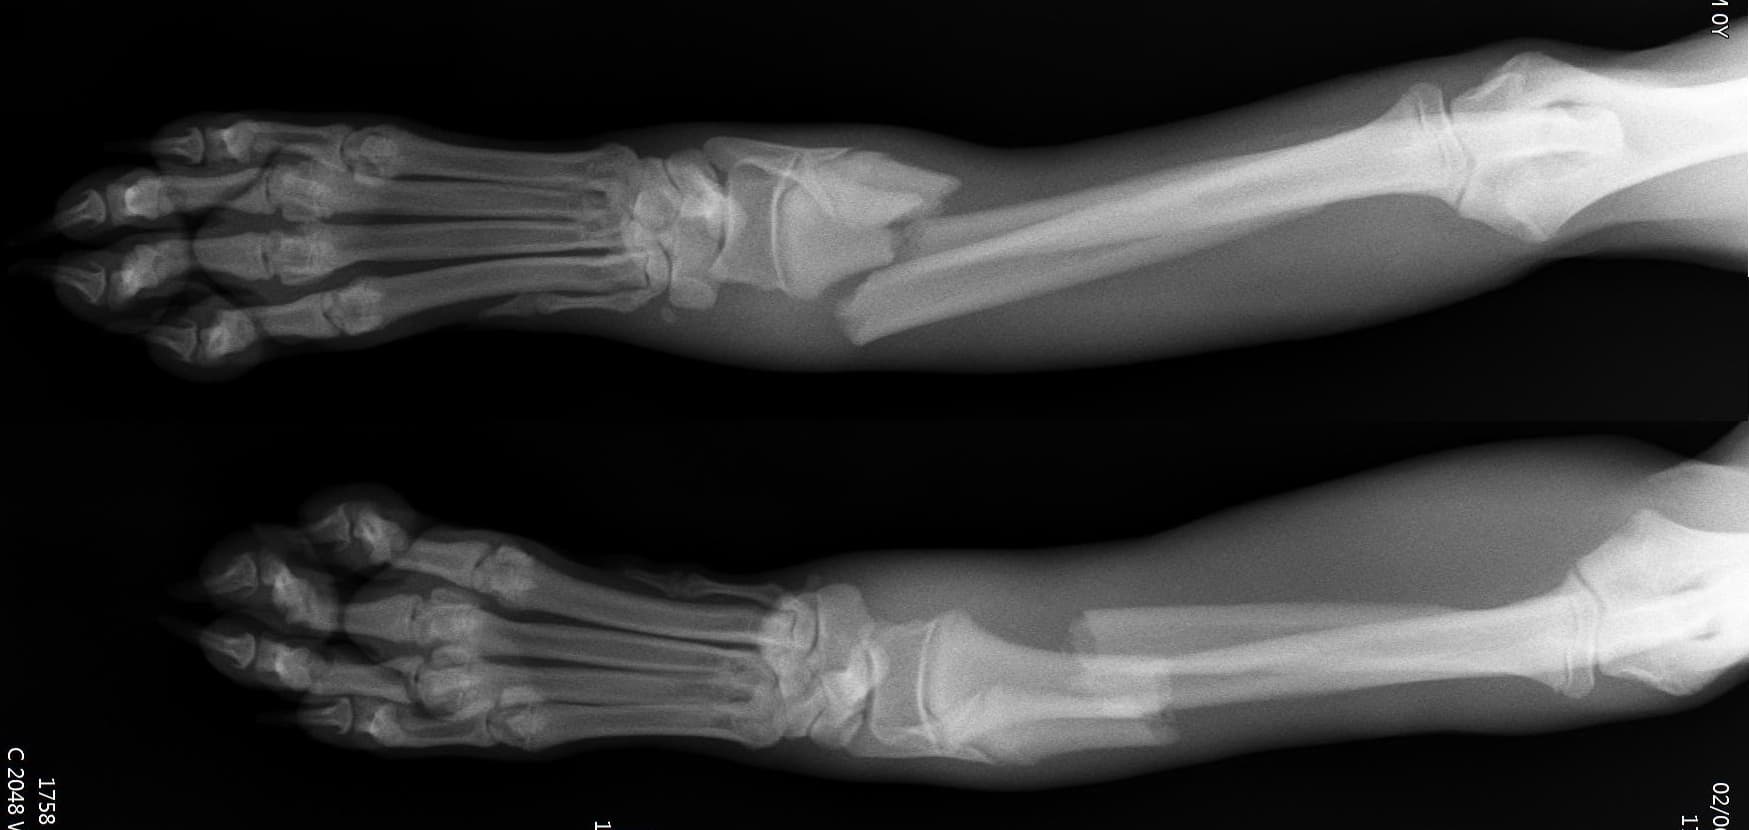

0164 채널 CT 촬영을 통해서 신속하게 고화질 영상을 얻어, 종양 유래 확인 및 전이 평가, 간문맥단락증(PSS), 선천적 뼈 기형과 같은 심화된 진단을 할 수 있습니다.

13수술 중 골절 상태 혹은 이식물 적용 후 상태 등 육안으로 명확히 확인하기 힘든 상태를 X-ray 확인하여 정확한 수술 결과를 만들어 내는 것이 가능